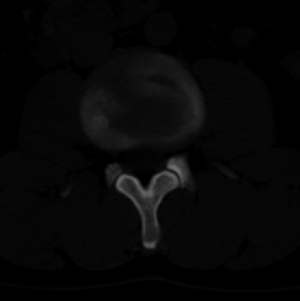

男,20,士兵,腰痛3年多,无外伤史

都是同一幅图啊,椎体内椎间盘突出。

支持!并多个椎体形成:“许莫氏”结节!

:“许莫氏”结节

考虑:1、多发许莫尔氏结节形成;

1、多发许莫尔氏结节形成;

许莫氏结节

1、多发许莫氏结节。